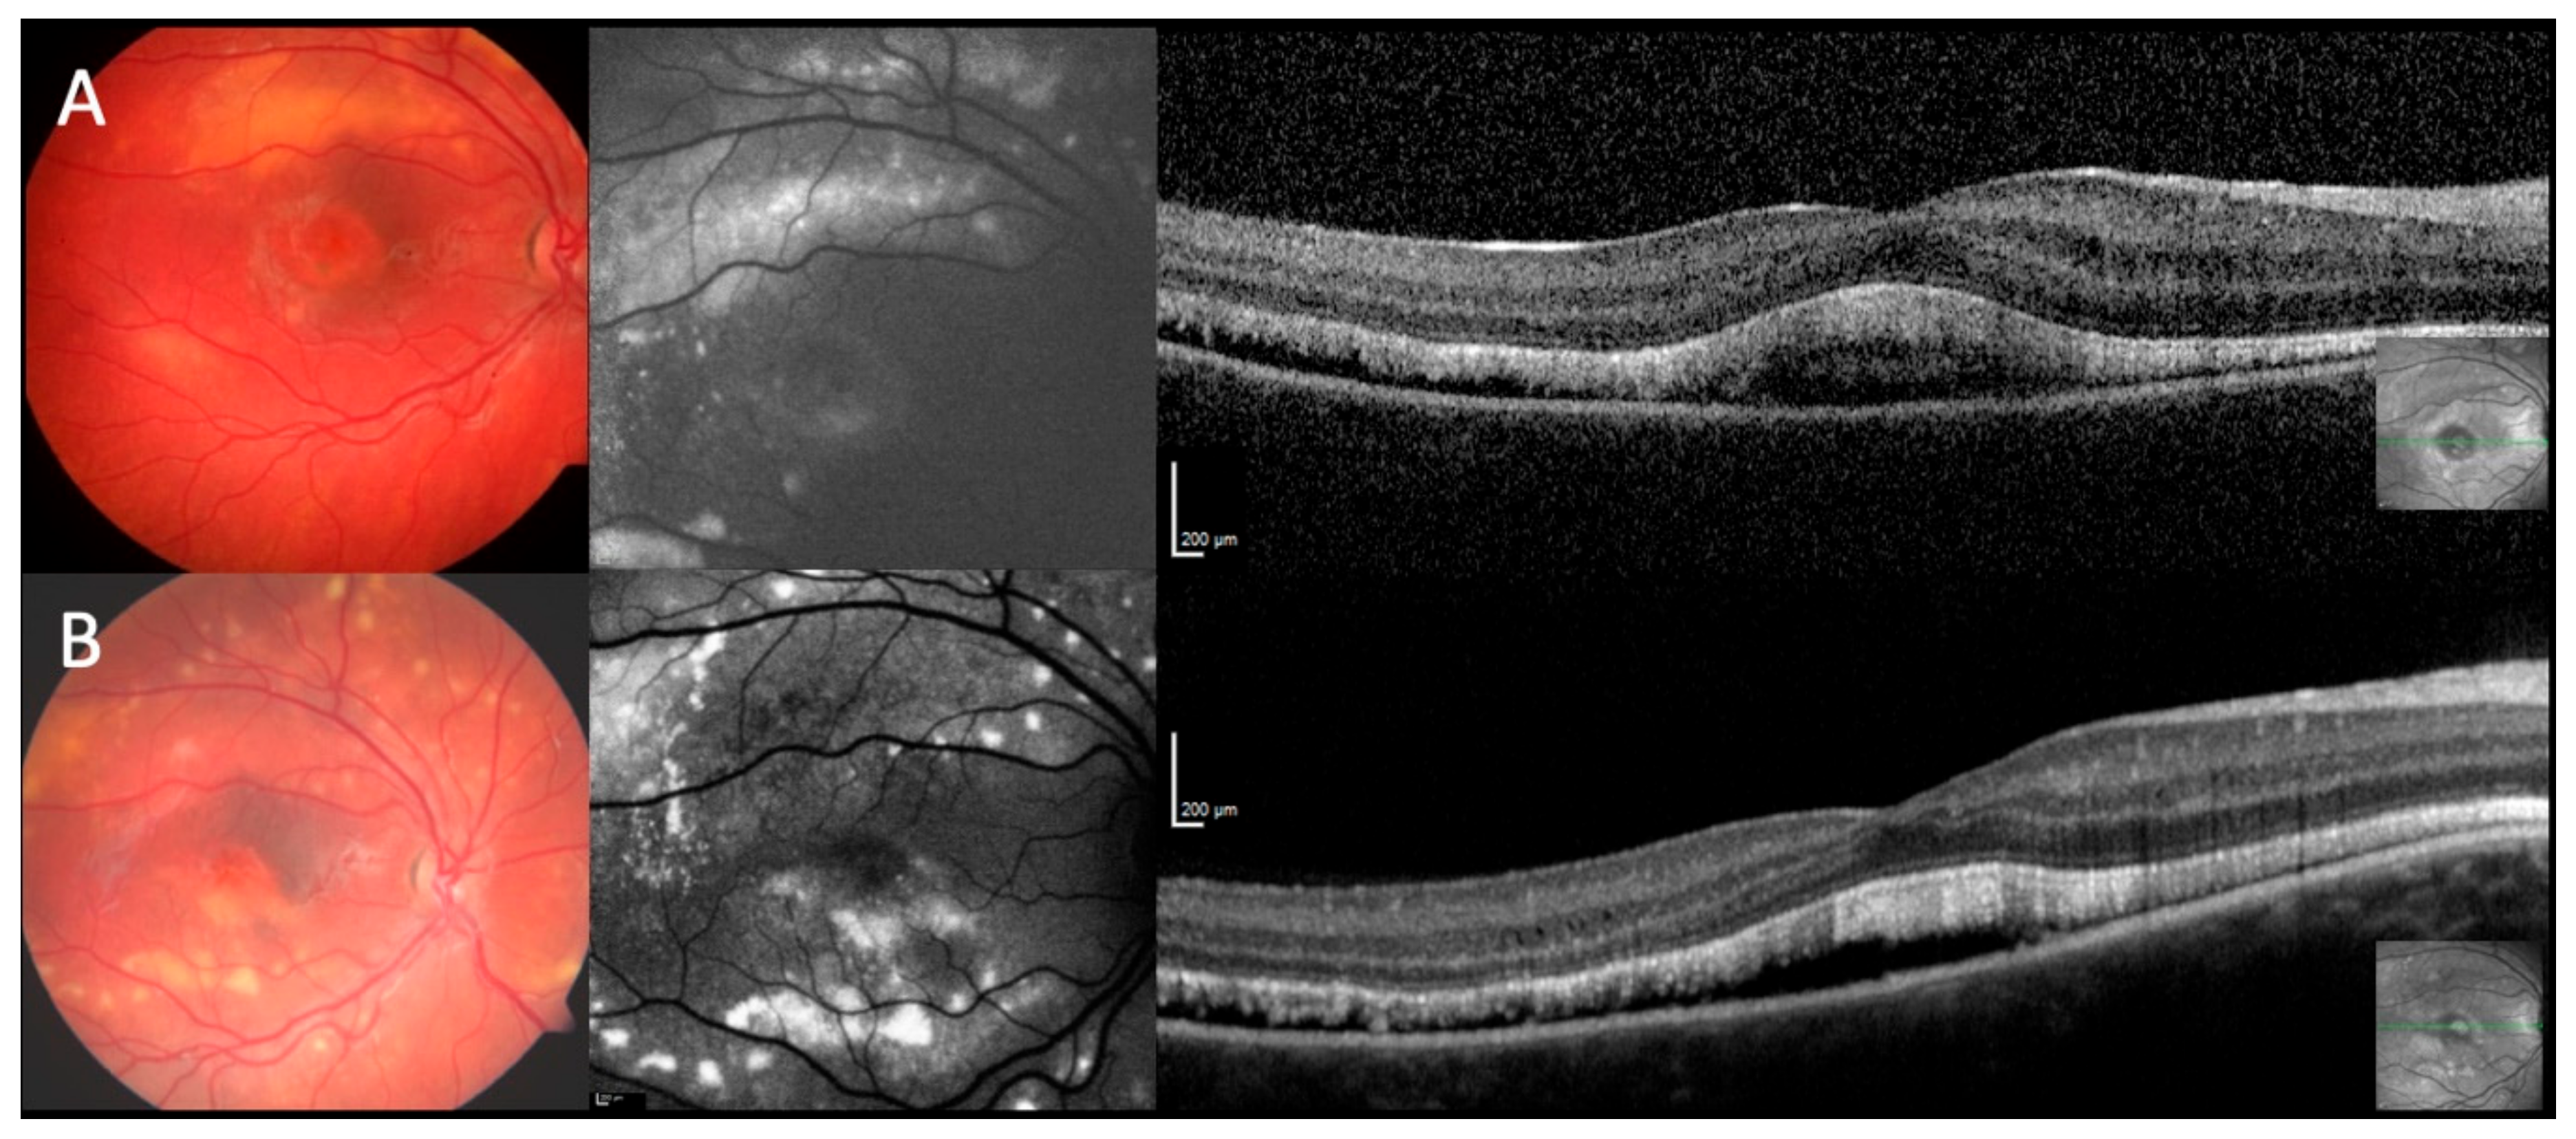

The ophthalmoscopic and retinal imaging findings separated the patients into five different phenotypes. The phenotype was similar on both eyes of each patient except for patient #16. The predominant phenotype I (19/36 eyes; #1–5, #7, #10, #12, #16 OS, #17) was characteristic for ARB: multiple fleck-like and often confluent yellow lesions involving the posterior pole and extending to the mid-periphery beyond the vascular arcades and nasal of the disc (Figure 1A). Phenotype II was different (8/36; #8, #9, #13, #14) with multiple small fleck-like, mostly non-confluent, yellow lesions involving the posterior pole and extending to the far periphery (Figure 1B). In one patient (2/36 eyes; #15) a continuous yellowish area without flecks extended partly into the far periphery and was bordered by a sharp demarcation towards the periphery (phenotype III; Figure 1C). More localized lesions resembling BVMD were seen in four patients with either one lesion at the posterior pole (phenotype IV, 2/36; #11; Figure 1D) resembling unifocal BVMD, or two to four well-circumscribed lesions consistent with multifocal BVMD (phenotype V, 5/36; #6, #16 OD, #18; Figure 1E). The phenotypes were similar in at least one eye of the two siblings of two families (#4/#12 and #16/#17), However, in family F5, patient #5 showed the characteristic ARB phenotype I, her sister (#6) presented with phenotype V. Similar phenotypes were seen at different years of age, therefore the different phenotypes cannot be explained as different stages of the same disease. Independent of the phenotype some eyes (14/36) showed a variable number of pigmented spots (#1, #2 OD, #7, #8, #9, #11, #15 OS, #17).

Figure 1. Autosomal recessive bestrophinopathy phenotypes I-V: Fundus photography and fundus autofluorescence (FAF): (A). (#5) multiple fleck-like and often confluent yellow lesions involving the posterior pole and extending to the mid-periphery beyond the vascular arcades and nasal of the disc. (B) (#8) multiple small fleck-like, mostly non-confluent yellow lesions involving the posterior pole and extending to the far periphery. (C) (#15) a continuous yellowish area without flecks extended partly into the far periphery and was bordered by a sharp demarcation line. (D) (#11) one Best vitelliform macular dystrophy (BVMD)-like lesion at the posterior pole resembling unifocal BVMD. (E) (#18) two well-circumscribed lesions consistent with multifocal BVMD.